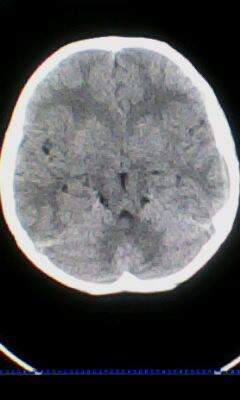

标题: PED3324:男 10岁 右侧 眼不自主抽动 自感颈部不适 [打印本页]

标题: PED3324:男 10岁 右侧 眼不自主抽动 自感颈部不适

蛛网膜下腔出血。

蛛网膜下腔出血可能。

颅脑ct轴位平扫颅内未见明确异常;建议必要时行mri检查。

窗调的不好,图像感觉怪怪的,不好说有什么明显异常,可建议mri检查。

颅脑ct轴位平扫颅内未见明确异常。